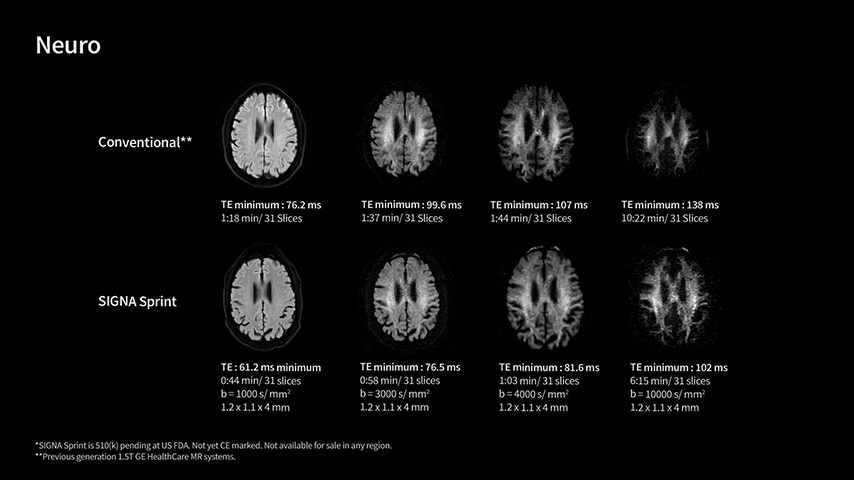

In oncological assessments, diffusion imaging is a critical clinical indicator. SIGNA Sprint offers clearer diffusion, reduced distortion, and improved SNR.¹

Within cardiovascular diseases, the functional assessment of the heart is an essential imaging application. SIGNA Sprint is powered by built-in AI technologies—Sonic DL™, AIR Recon DL and AIR x™—enabling high-quality imaging even in the most demanding anatomies.

The growing clinical need within oncology and cardiology requires an MRI scanner that can rise to the challenge. With a high gradient performance of 65/200, SIGNA Sprint helps deliver crystal-clear imaging for ultimate diagnostic confidence. Improved signal-to-noise ratio (SNR) and diffusion, with deep-learning solutions that could enhance diagnostics and treatment response monitoring in your oncology patients.¹ Additionally, the shift from qualitative to quantitative cardiac MRI reduces the time and expertise needed to interpret scans and offers greater consistency and reliability. Helping you to unlock the power to explore further - even in your most challenging cases.

With GE HealthCare's comprehensive suite of deep-learning solutions integrated into SIGNA Sprint, you can unlock the full potential of your MRI system. No need for complicated patient setups or imaging protocols. The exceptional intelligence of our AI solutions offer multiple benefits, with AIR Recon DL giving pin-sharp images, Sonic DL accelerating scans up to 12x, and AIR x enabling automated slice placement. All helping to enhance your department’s workflow efficiency, increase patient throughput, and get the diagnostic clarity you need, faster.¹ Meaning you can spend more time on what truly matters—personalized patient care, enabling optimized treatment plans and treatment response monitoring—ultimately, supporting better clinical outcomes.